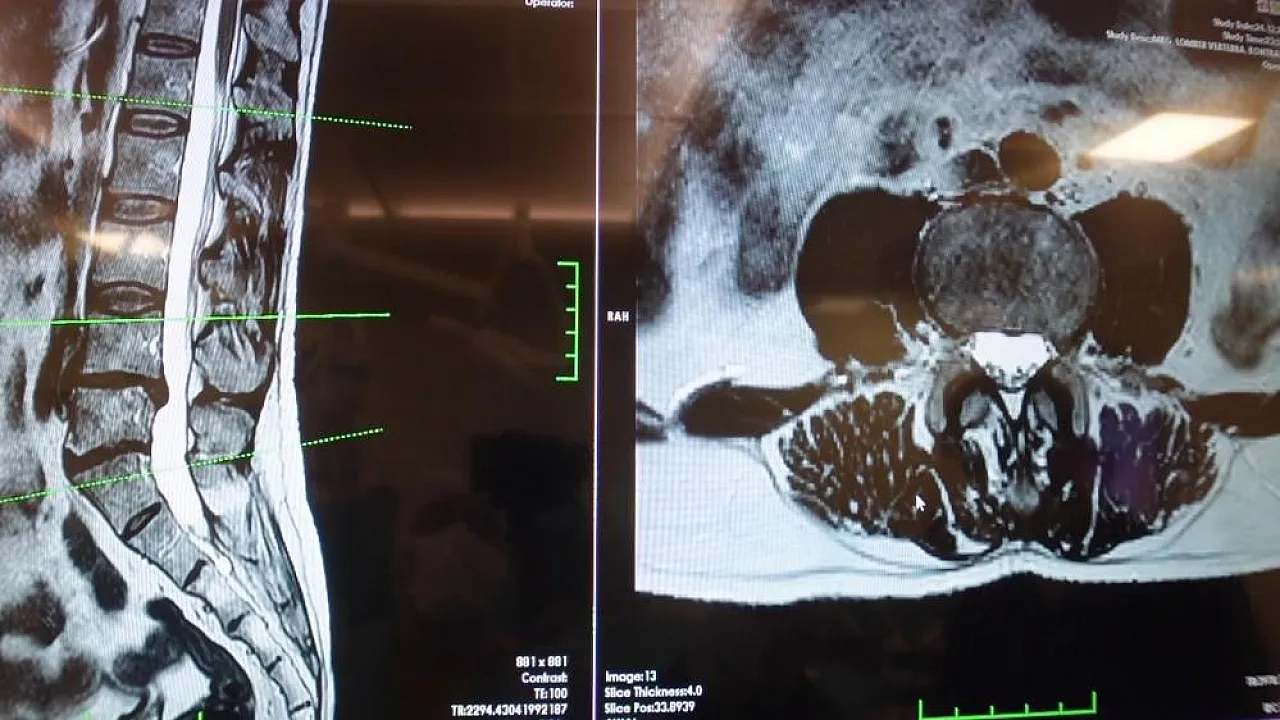

Omurga rahatsızlıklarının Beyin ve Sinir Cerrahisi pratiğinde en sık karşılaşılan sorunların başında geldiğini belirten Prof. Dr. Erol, özellikle bel bölgesine yoğunlaşan ağrıların her zaman cerrahi müdahale gerektirmediğini vurguladı. Kaslar, eklemler ve bağ dokularının uzun süreli zorlanması sonucu ortaya çıkan mekanik bel ağrılarının, fıtıkla karıştırılmaması gerektiğini ifade eden Erol, "Mekanik ağrılar toplumda fıtıktan çok daha yaygın görülüyor" dedi.

Omurga hastalıkları arasında bir diğer tehlikeli grubun ise omurilik kanal darlığı olduğunu dile getiren Prof. Dr. Erol, bu durumun genellikle yaşa bağlı olarak geliştiğini belirtti. Daralma sonucu sinirlerin sıkıştığını ve yürüme mesafesinin kısaldığını ifade eden Erol, "Bu hastalar yürürken bacaklarına yayılan ağrı hisseder ve oturup dinlenme ihtiyacı duyarlar" diyerek, bu şikayetlerin ciddiye alınması gerektiğini vurguladı.